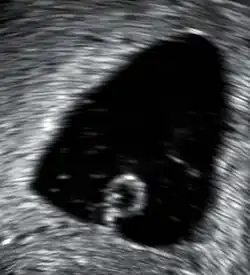

| Método de diagnóstico | Exame, gonadotrofina coriónica humana, ecografia[8] |

Entre os fatores de risco para um aborto espontâneo estão a gravidez em idade avançada, ter antecedentes de aborto, a exposição ao fumo de tabaco, obesidade, diabetes, problemas de tiroide e consumo de drogas ou álcool.[5][6] Cerca de 80% dos abortos espontâneos ocorrem durante as primeiras 12 semanas de gravidez, ou primeiro trimestre.[1] Em cerca de metade dos casos, a causa subjacente envolve anomalias cromossómicas.[4][1] O diagnóstico de um aborto espontâneo consiste geralmente num exame para verificar se o colo do útero se encontra aberto ou encerrado, análises ao sangue para avaliar os níveis de gonadotrofina coriónica humana e uma ecografia.[8] Entre outras condições que podem manifestar sintomas semelhantes estão uma gravidez ectópica e hemorragia de nidação.[1]